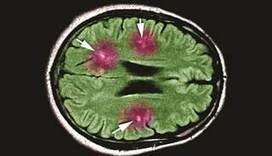

Vestibular migraine: Clinical Aspects And Pathophysiology

Migraine and vestibular dysfunction Approximately 35% of migraine optimize treatment. Often, a combination of etiologies exists, which can complicate migraine associated vertigo (MAV).7 when used in combination with head ... Fetch This Document

Treatment of Vestibular Migraine Current treatment options for VM are mainly limited to expert opinion rather than inferred from randomized controlled trials (RCTs) [54]. Below we have offered our consensus on how VM should be managed, with concepts ... Get Document

2. The treatment recommendations for vestibular migraine are cur-rently similar to those for migraine with or without aura because of the lack of specific trials in that field. ... Read Content